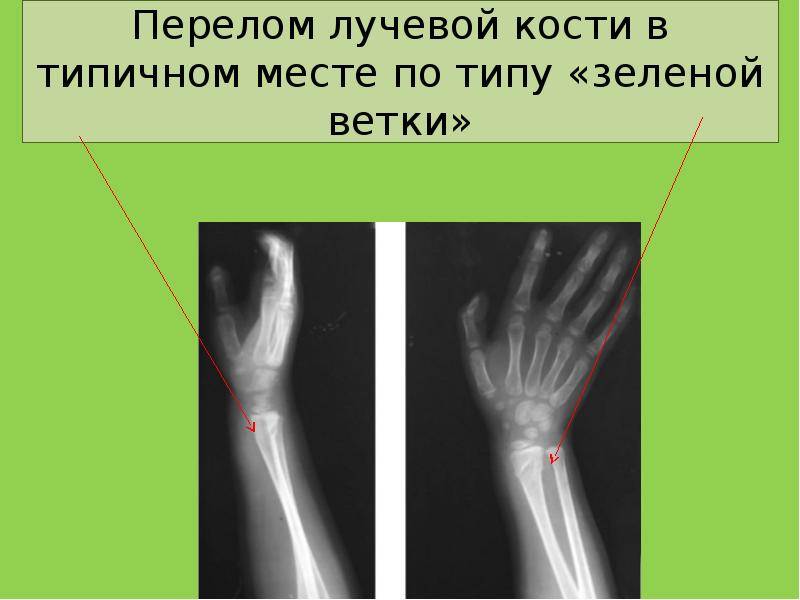

В костных тканях ребенка гораздо больше воды и органических соединений, чем у взрослого человека, и меньше минеральных солей, что помогает так называемым «зонам роста» из хрящевых структур, расположенных между костными сочленениями, обеспечивать постоянный рост костей. Такая особенность обуславливает вероятное возникновение переломов, характерных только для детского возраста. К ним относятся:

- надлом по типу «зеленой ветки», когда ткани разрываются только с одной стороны, а с другой надкостница остается целой; поднаткостничный перелом, когда костные структуры повреждены, но прикрыты нетронутой надкостницей; разрывы различного характера, произошедшие вдоль линии хрящевых зон роста (эпифизиолизы, остеоэпифизиолизы и метаэпифизиолизы); апофизиолизы – отрывы по линии крепления мышечных волокон.

Для детей характерны переломы, при которых надкостница не повреждается. Они получили условное название «перелом по типу зелёной ветки». Кроме того, часто встречаются травмы в месте ростковой зоны кости, где процессы окостенения ещё не завершились. Такие травмы называются эпифизеолизами.

Чаще всего у детей происходят переломы по типу зелёной ветки